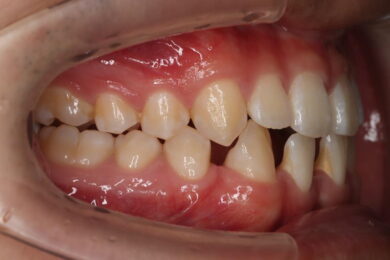

• インビザライン終了後、インプラント2本埋入2週間後

初めにマウスピース矯正「インビザライン」による術前矯正を11か月行いました。各隙間を寄せ、インプラントを埋入するスペースを確保し、適切な咬合関係を確立します。

インビザラインの治療計画では、下顎前歯がより美しく審美的に並ぶよう、ご自身の歯とインプラントの歯がほぼ同じ幅径になるよう計算し配列を行いました。